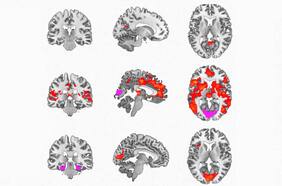

Reino Unido autorizó la realización de pruebas para determinar si la Dimetiltriptamina, con efectos alucinógenos, tiene usos positivos en los tratamientos de pacientes con trastornos psiquiátricos y psicológicos. Según Carol Rutledge, la directora científica y médica de Small Paherma, quien lidera el ensayo, el DMT "deshace lo que ha sido causado por el estrés que ha pasado o los pensamientos depresivos que tiene el paciente, y aumenta enormemente la creación de nuevas conexiones".

Droga psicodélica DMT podría ser usada para tratar la depresión